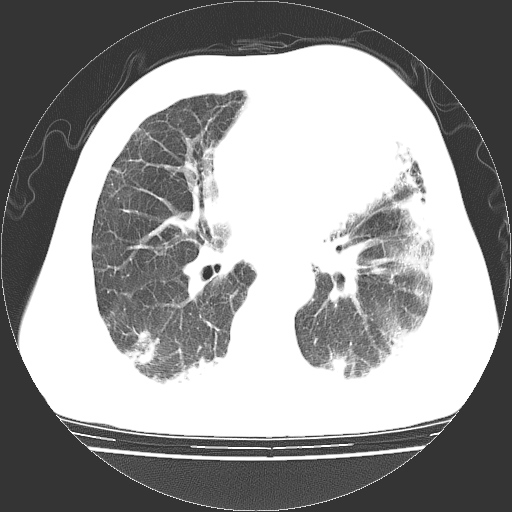

标题: CT25149:男,69岁,反复咳嗽、咳痰五年余,呼吸困难三天。 [打印本页]

男,69岁,反复咳嗽、咳痰五年余,呼吸困难三天。

慢支伴感染、肺气肿、肺心病!支持!另:间质纤维化!

两肺间质性炎症并感染,左上叶肉芽肿

考虑慢性间质性肺炎并肺间质纤维化。

慢支伴感染、肺气肿、肺心病。双肺间质性改变(间质纤维化)。